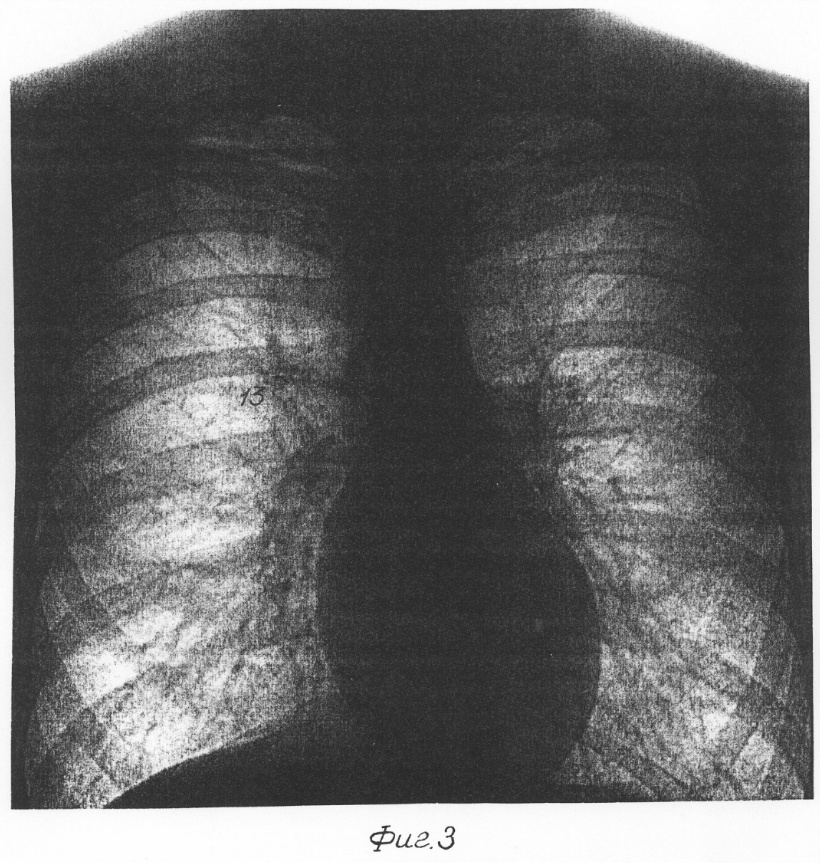

(57) Реферат: Изобретение относится к медицине, а именно к рентгенодиагностике, и предназначено для работы с цифровыми рентгеновскими изображениями, способ предназначен для использования, преимущественно, в противотуберкулезных учреждениях с целью своевременного выявления легочной патологии. Кроме того, способ эффективен при рентгенологическом контроле терапевтического лечения. Способ рентроспективного анализа рентгеновских изображений легких предусматривает рентгенографию одного и того же пациента дважды при тех же энергетических и геометрических режимах съемки через определенный интервал времени и сравнение полученных изображений, при этом рентгеновское цифровое изображение формируют посредством ЭВМ в виде матрицы оптических плотностей объекта изображения, производят совмещение цифровых изображений по элементам позвоночника до полного совпадения идентичных позвонков, а диапазон оптических плотностей по центру и ширине выбирают соответствующим оптимальному для наблюдения костных структур. Затем производят вычитание идентичных фрагментов на первом и втором цифровом изображениях и результирующее цифровое изображение выводят на экран дисплея в диапазоне оптических плотностей, по центру и ширине оптимальном для наблюдения легочной ткани. Клинические изменения определяют по величине остаточных элементов результирующего изображения, превышающих 2-3 мм. Изобретение позволяет обеспечить возможность осуществления ретроспективного анализа легких на цифровых флюорографических аппаратах. 3 ил. Предлагаемое изобретение относится к медицине, а именно к рентгенодиагностике, и предназначено для работы с цифровыми рентгеновскими изображениями. Известен способ ретроспективного анализа рентгеновских снимков легких, предусматривающий рентгенографию одного и того же пациента в идентичных условиях с интервалом от месяца до года и последующей взаимной стереоскопической обработкой снимков при их синхронном вращении [1]. Известен также способ ретроспективного анализа рентгеновских сигналов легких, предусматривающий рентгенографию одного и того же пациента в идентичных условиях через определенный интервал времени с последующей взаимной стереоскопической обработкой снимков при освещении одного из них прерывистым световым потоком [2]. Этот способ был выбран нами в качестве прототипа. Основным недостатком известных аналогов [1, 2] является то, что они не могут быть использованы при ретроспективном анализе цифровых изображений, полученных на современных флюорографах, где рентгеновское изображение воспроизводится на экране видеомонитора. Техническим результатом, достигаемым при использовании настоящего изобретения, является обеспечение возможности осуществления ретроспективного анализа рентгеновских снимков легких на цифровых флюорографических аппаратах. Данный технический результат достигается тем, что в способе ретроспективного анализа рентгеновских изображений легких, предусматривающем рентгенографию одного и того же пациента дважды при тех же энергетических и геометрических режимах съемки через определенный интервал времени, и сравнение полученных изображений, рентгеновское цифровое изображение формируют посредством ЭВМ в виде матрицы оптических плотностей объекта изображения, производят совмещение цифровых изображений по элементам позвоночника до полного совпадения идентичных позвонков, а диапазон оптических плотностей по центру и ширине выбирают соответствующим оптимальному для наблюдения костных структур. Затем производят вычитание идентичных фрагментов на первом и втором цифровом изображениях и результирующее цифровое изображение выводят на экран дисплея в диапазоне оптических плотностей, по центру и ширине оптимальном для наблюдения легочной ткани. Клинические изменения определяют по величине остаточных элементов результирующего изображения, превышающих 2-3 мм. В дальнейшем изобретение поясняется чертежами и описанием к ним. На фиг. 1 показана схема получения первого (фиг. 1, а) и второго (фиг. 1, б) изображений легких одного и того же пациента на цифровом флюорографе. На фиг. 2 приведены основные операции предлагаемого способа ретроспективного анализа рентгеновских изображений легких. Фиг. 2, а – наложение первого и второго изображений; фиг. 2, б – полное совмещение изображений; фиг. 2, в – взаимное вычитание идентичных фрагментов изображений; фиг. 2, г – нанесение обнаруженной патологии на второе изображение. На фиг. 3 приведен практический пример. Ретроспективный анализ рентгеновских изображений легких обычно проводится во фтизиатрии с целью выявления незначительных патологических изменений в легочной ткани, вызванных туберкулезом, раком и другими заболеваниями. Предложенный способ ретроспективного анализа рентгеновских изображений легких осуществляется на цифровом рентгенодиагностическом аппарате, например флюорографе. Основными компонентами цифрового флюорографа являются рентгеновский излучатель 1, подключенный к рентгеновскому питающему устройству 2, и цифровая флюорографическая камера 3, соединенная с блоком обработки цифрового сигнала (ЭВМ) 4, с которым связан видеомонитор 5 (фиг. 1). Во время экспозиции пациент 6 занимает стандартное положение перед цифровой флюорографической камерой 3. При этом грудь пациента 6 примыкает к входному окну камеры 3, а голова, руки и ноги фиксируются с помощью штатных устройств (на чертежах не показаны). Рентгенография легких выполняется на определенной фазе дыхания при определенных энергетических параметрах в импульсном режиме. Рентгеновское изображение легких формируется ЭВМ 4 в цифровом виде 7 (фиг. 1, а). Из оперативной памяти ЭВМ 4 цифровое изображение 7 поступает на экран видеомонитора 5, где анализируется рентгенологом. Далее цифровое изображение легких поступает в цифровой архив на длительное хранение. Каждый снимок сопровождают данные о пациенте и о режимах рентгенографии. Цифровой архив находится в рентгеновском отделении. Обычно цифровые рентгеновские снимки хранятся на магнитооптических дисках емкостью 640 мГб. Один такой диск содержит до 500 изображений. Повторная флюорография легких того же пациента 6 выполняется через год на том же цифровом флюорографе при тех же энергетических и геометрических режимах съемки, что и первый снимок. Полученное изображение легких 8 (фиг. 1, б) анализируется совместно с первоначальным снимком 7, который поступает в ЭВМ 4 из цифрового рентгеновского архива. Необходимо отметить, что при регистрации цифровой флюорографической камерой 3 рентгеновского излучения в памяти ЭВМ формируется матрица, отражающая плотностные характеристики изучаемого объекта в диапазоне чисел от 0 до 16000. Для детального изучения столь широкого диапазона плотностных характеристик исследуемого объекта всю шкалу динамического диапазона можно разбить на отдельные “окна” посредством установки центра и ширины окна. При этом цифровые значения внутри выбранного окна преобразуются в цвета монитора с формированием градаций серой шкалы. Выбор центра и ширины оптического окна достигается путем верхнего и нижнего уровней визуализации. При этом пиксели, плотностные характеристики которых располагаются в диапазоне от верхнего и нижнего уровня (ширина окна), преобразуются в полутона серого цвета. От выбора ширины окна зависит контрастность изображения: узкому окну соответствует высокая контрастность и наоборот. Центр оптического окна должен определяться структурой изучаемых тканей. Цифровые изображения органов грудной клетки 7 и 8 пациента 6 выводятся одновременно на экран видеомонитора 5 (фиг. 2, а). Далее производится взаимное совмещение изображений по элементам позвоночника 91, 92. до полного совпадения идентичных позвонков 91,2 (фиг. 2, б). При этом центр и ширина оптического окна динамического диапазона должны быть оптимальными для наблюдения костных структур. Через это оптическое окно легочные ткани и сосуды не наблюдаются. На данном этапе этот факт является положительным, так как разгружает рентгеновскую картину и способствует повышению точности операции по совмещению изображений 7 и 8. Совмещение изображений идентичных фрагментов позвоночника выполняется рентгенологом вручную путем взаимного перемещения первого и второго изображений на экране дисплея 5. После окончания этой операции (фиг. 2, б) в автоматическом режиме по специальной программе, заложенной в ЭВМ, производится вычитание идентичных фрагментов на первом и втором изображениях. Результирующее изображение 10 выводится на экран дисплея 5 в диапазоне оптических плотностей, оптимальном для наблюдения легочной ткани. Через это оптическое окно наблюдается шумовой фон в виде россыпи мелких точек 11 и остаточное изображение 12, вызванное патологическим изменением в легких на повторном изображении 8 (фиг. 2, в). При этом на более раннем изображении 7 патологических изменений нет. Опыт показывает, что на результирующем изображении 10 надежно выявляются остаточные изменения 12, превышающие 2-3 мм. При отсутствии клинических изменений на втором изображении 8 остаточные изменения 12 на результирующем изображении 10 не проявляются. Для повышения точности диагностики взаимное совмещение и вычитание изображений может производиться неоднократно, при этом выбирается результирующее изображение с меньшим шумом. Обнаруженную патологию 12 окрашивают, например, в красный цвет 13 и воспроизводят на втором изобретении 8 (фиг. 2, г). Ниже приведен клинический пример применения нового способа ретроспективного анализа рентгеновских снимков легких. Пациент Д. 1980 г. рождения прошел в 2000 г. профилактическое обследование легких в Новомосковском противотуберкулезном диспансере на малодозовом цифровом флюорографе “Ренекс-Флюоро”. При анализе цифрового снимка легких отклонения от нормы не обнаружено (легочные поля прозрачные, легочный рисунок не изменен, корни структурные, синусы свободные). В 2001 г. пациент Д прошел повторное рентгенологическое обследование легких. Съемка выполнялась на том же цифровом флюорографе “Ренекс-Флюоро” в тех же геометрических условиях и энергетических режимах, что и в первом случае. Ретроспективный анализ рентгеновских снимков легких проводился согласно условиям нового способа. Было выявлено незначительное уплотнение 13 в средней зоне правого легкого (фиг. 3). Дальнейшее клиническое обследование пациента Д. показало, что оно вызвано туберкулезным процессом. Источники информации 1. SU №833202, МПК7 А 61 В 6/00, 1979 г. 2. SU №959756, МПК7 А 61 В 6/00, 1980 г. Формула изобретения Способ ретроспективного анализа рентгеновских изображений легких путем рентгенографии одного и того же пациента дважды при тех же энергетических и геометрических режимах съемки через определенный интервал времени и сравнение полученных изображений, отличающийся тем, что рентгеновское цифровое изображение формируют посредством ЭВМ в виде матрицы оптических плотностей объекта изображения, производят совмещение цифровых изображений по элементам позвоночника до полного совпадения идентичных позвонков, при этом диапазон оптических плотностей по центру и ширине выбирают соответствующим оптимальному для наблюдения костных структур, затем производят вычитание идентичных фрагментов на первом и втором цифровых изображениях и результирующее цифровое изображение выводят на экран дисплея в диапазоне оптических плотностей по центру и ширине, оптимальном для наблюдения легочной ткани, клинические изменения определяют по величине остаточных элементов результирующего изображения, превышающей 2-3 мм. РИСУНКИ